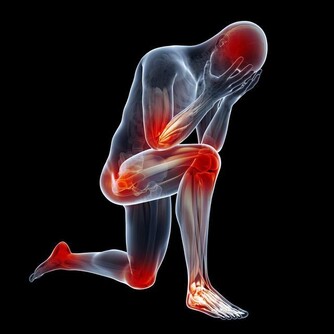

然而,在某些情況下,高血壓可能會顯示出一些症狀,這可能表明你需要去看醫生了。這九個需要注意的標誌,包括頭痛、呼吸短促、頭暈、胸痛、心悸、鼻出血、胃痛、發燒和視力模糊。其中一些症狀,比如頭痛和頭暈等,跟高血壓有較為明顯的關係,雖然你經常忘記把它們聯想在一起。

但還有一些跡像看起來似乎很難跟高血壓聯繫起來,但它們確實有關係。

比如,眼部問題和噁心,可能是血壓過高或大腦壓力增加的特殊跡象。